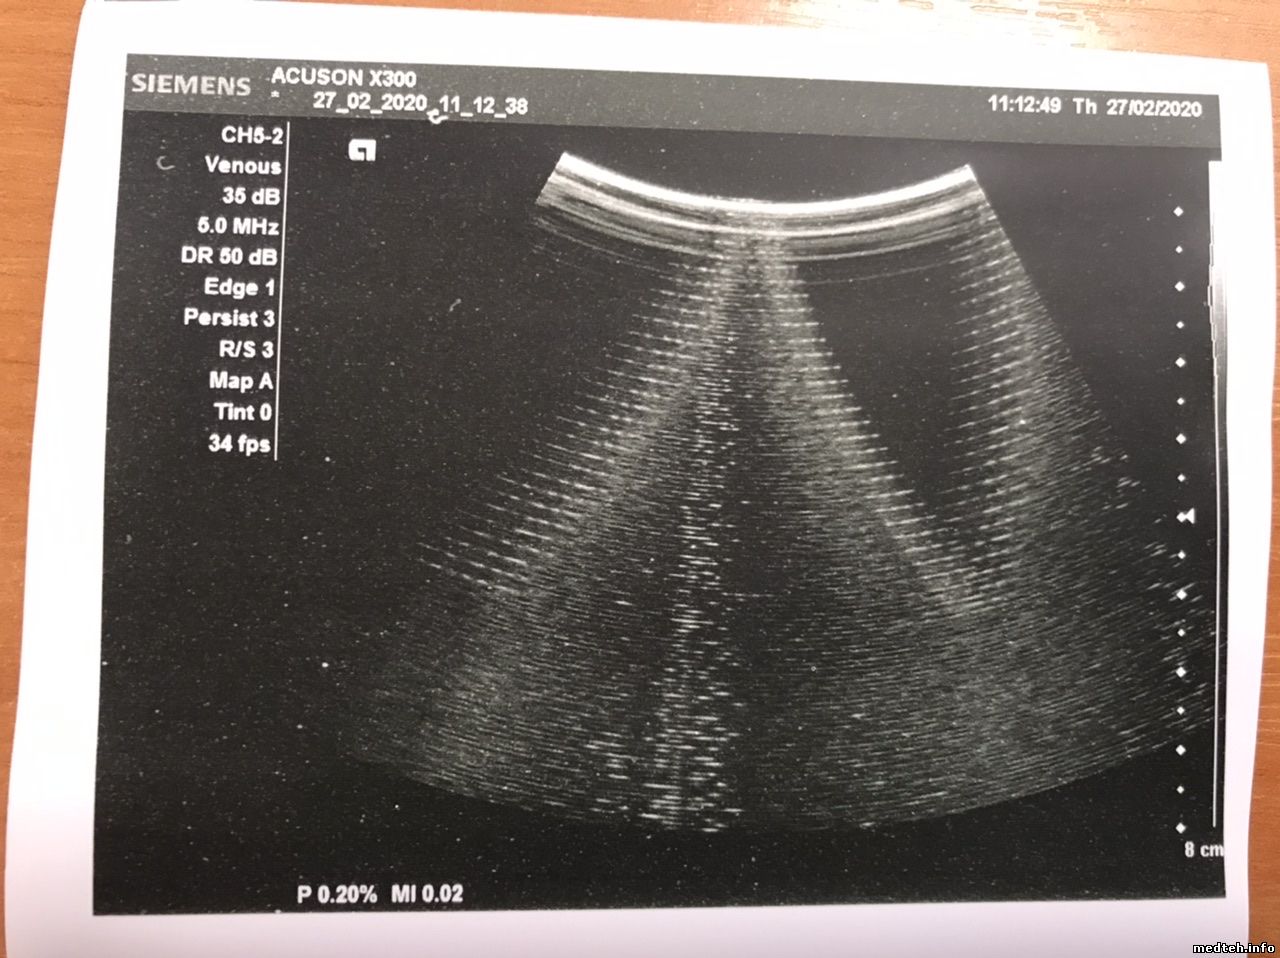

Уважаемые коллеги!

Помогите понять, откуда такая помеха на конвексном датчике и как с ней бороться?

Заранее спасибо!

4217815.jpg (173.0 Kb)

Цитата ЮраВо ()

откуда такая помеха

Попробуйте подключить от бесперебойника. Или без него напрямую ...